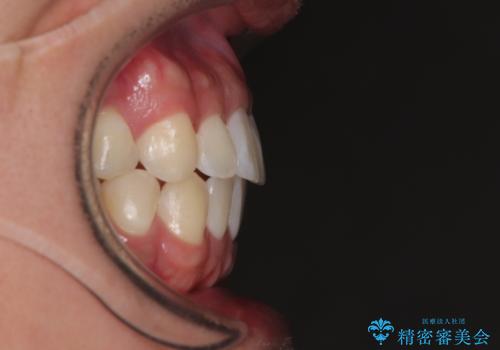

- 前歯の反対咬合などを気にして来院された患者様です。

ワイヤー矯正、マウスピース矯正どちらでも対応可能であったので、ご本人の希望によりインビザラインにて矯正治療を行うこととしました。

マウスピース矯正は、ワイヤー矯正と違い、とにかく自己管理が非常に重要となります。

毎日の装着時間をしっかりと守ってくださり、1年強の短期間で、あっという間に治療を終えることができました。